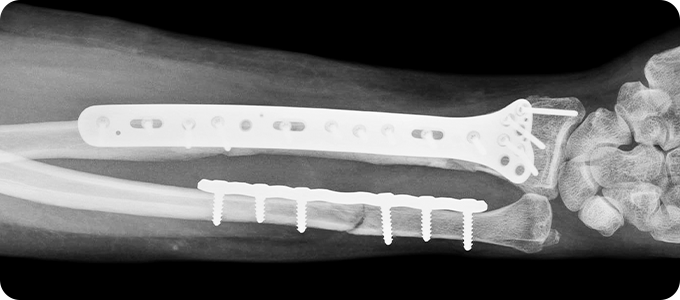

상지골절

상지골절 이미지

• 위팔 골절, 쇄골 골절, 손목 골절은 손을 짚으면서 넘어질 때,

팔을 곧게 뻗은 채로 넘어질 때나, 교통사고, 타박 등에 의해 발생합니다.

골다공증 등으로 인해 뼈가 약해진 분에게 더 쉽게 발생할 수 있습니다.

상완골 골절 수술

X-ray 및 CT를 통해 골절 형태와 전위 정도를 확인합니다.

골절된 뼈를 원래 위치로 맞추는 정복 작업을 진행합니다.

금속판, 나사, 고정막을 이용해 뼈를 고정합니다.

손 뼈 골절 수술

손은 작은 뼈들이 정교하게 연결되어 있어

골절 시 기능 손상이 크기 때문에,

정확한 정복과 고정이 중요합니다.